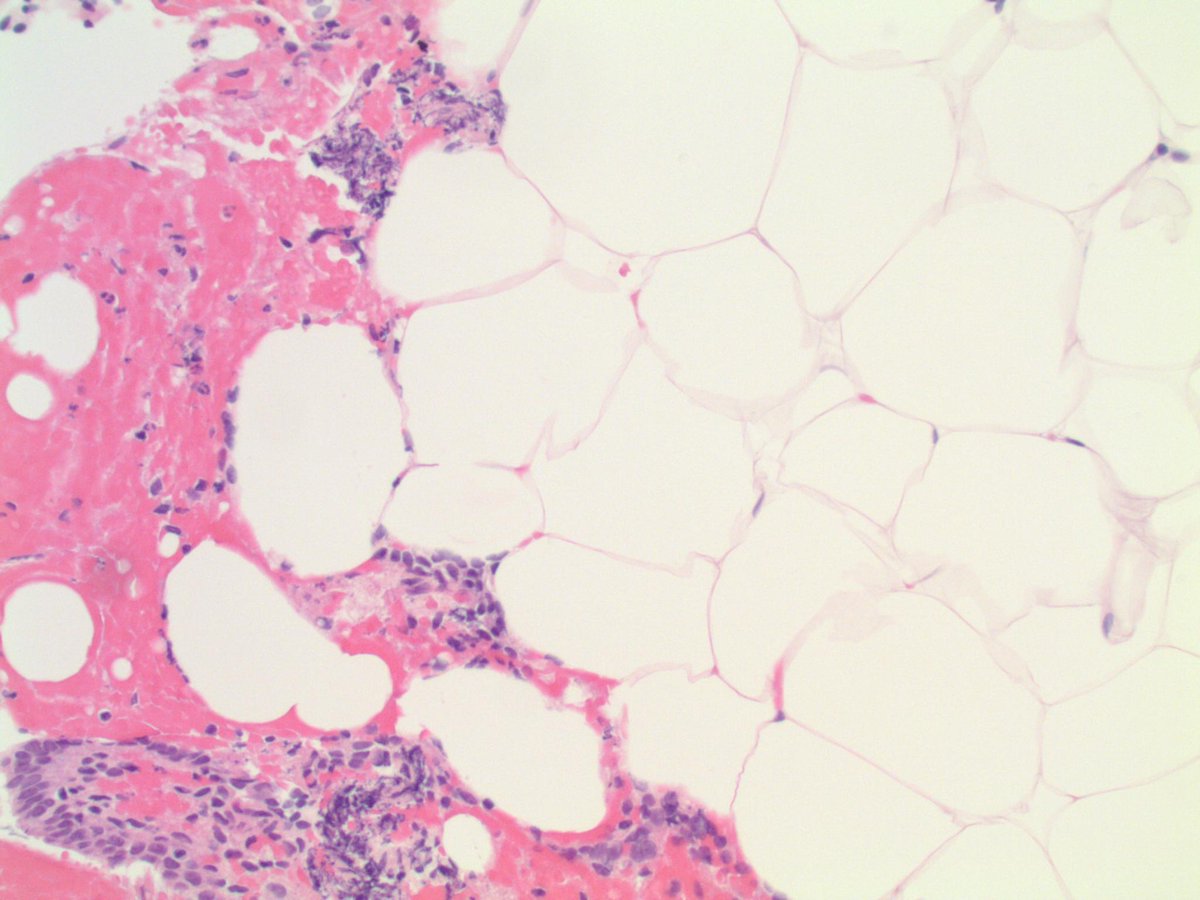

FIBROUS DYSPLASIA. NB: spindle-stellate cells; eosinophilic cytoplasm; monomorphic ovoid nuclei; irregularly-shaped woven bone trabeculae with incomplete osteoblastic rimming.

FIBROUS DYSPLASIA. NB: spindle-stellate cells;

eosinophilic cytoplasm; monomorphic ovoid nuclei; irregularly-shaped woven bone trabeculae with incomplete osteoblastic rimming.